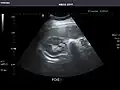

Abdominal Ultrasound (Full Exam)

STRUCTURED REPORT

(Technique: Transabdominal ultrasonography; Device: Toshiba Aplio XG)

Liver: Diffusely homogeneous and normal in echogenicity. No focal mass or contour nodularity. No intrahepatic biliary ductal dilatation.

Portal Vein: Patent main portal vein.

Gallbladder: No stones, wall thickening, or pericholecystic fluid.

Common Bile Duct: Nondilated measuring 1.3 mm at the level of the porta hepatis.

Pancreas: Visualized portions unremarkable.

Spleen: Normal in size.

Kidneys: Right and left kidneys measure 11.5 cm and 12 cm in length respectively. No hydronephrosis. Small left lower pole kidney cyst.

Ascites: None.

Aorta: Visualized portions normal in caliber, 16 x 15 mm.

IVC: Normal.

IMPRESSION:

Normal abdominal ultrasound.